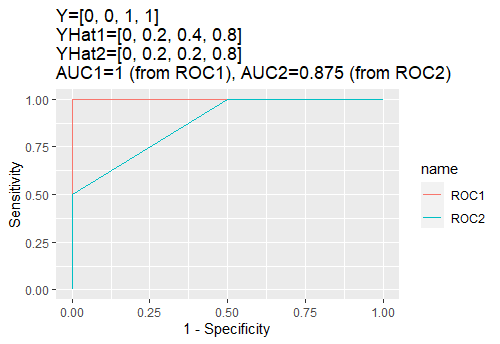

This subsection we present the experimental results. A brief summary of comparison of conventional methods literature and the proposed method is presented in Table 3. A detailed report of the proposed methodology is presented in Table 4. We also plot the AUC values for the proposed models in Figure 9.

This paper focuses on using Area-Under-Curve (or AUC) as the main evaluation metric. The AUC value is obtained from the Receiver Operating Characteristic (ROC) curve, a path constructed using different pairs of specificity and sensitivity.

Sensitivity and Specificity. The notion of sensitivity is interchangeable with recall or true positive rate. In a simple two-class classification problem, the goal is to investigate covariate matrix in order to produce an estimated value of . From the output of a Neural Network model, the predicted values are always between 0 and 1, which acts as a probabilistic statement to describe the chance an observation is class 1 or 0. Given a threshold between 0 and 1, we can compute sensitivity to be the following

| (9) |

On the other hand, specificity is also used to create ROC curve. Given a certain threshold between 0 and 1, we can compute specificity using the following

| (10) |

Given different thresholds, a list of pair of sensitivity and specificity can be created. The Area-Under-Curve (AUC) is the area under the path plotted using pairs of sensitivity and specificity that is generated using different thresholds.

|

Area-Under-Curve (AUC). The AUC value is a single number derived from a predicted probability by a classification rule and the true label [9]. Given a vector of true label and a vector of predicted probability , we can use statistical package “pROC”111The package is called “Display and Analyze ROC Curves”. Source: https://github.com/xrobin/pROC to assist this computation. The package uses automatically generated thresholds to convert into binary format. For example, we can use threshold of to convert a vector of predicted probabilities into binary form by writing . Let us assume the true label to be . Thus, we can compute specificity to be 1 and sensitivity to be 1. We can then change threshold to a different value to compute another pair of specificity and sensitivity. By tracking all pairs of specificity and sensitivity, we can generate a curve called Receiver Operating Characteristic (ROC) [9]. The value of Area-Under-Curve is exactly the area under the ROC. Assume the predicted probability to have some mistakes. In other words, let us assume the predicted probability vector to be . It is not possible for two observations to have the same probability predicted while they come from different classes. Therefore, there must be a mistake in one of them. This information is reflected using the same procedure. Please see Table 7.